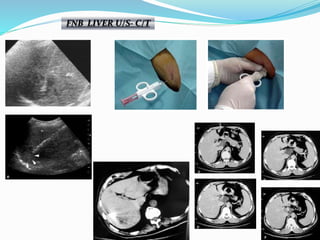

FNB LIVER U/S- C/T

FNB LIVER C/T